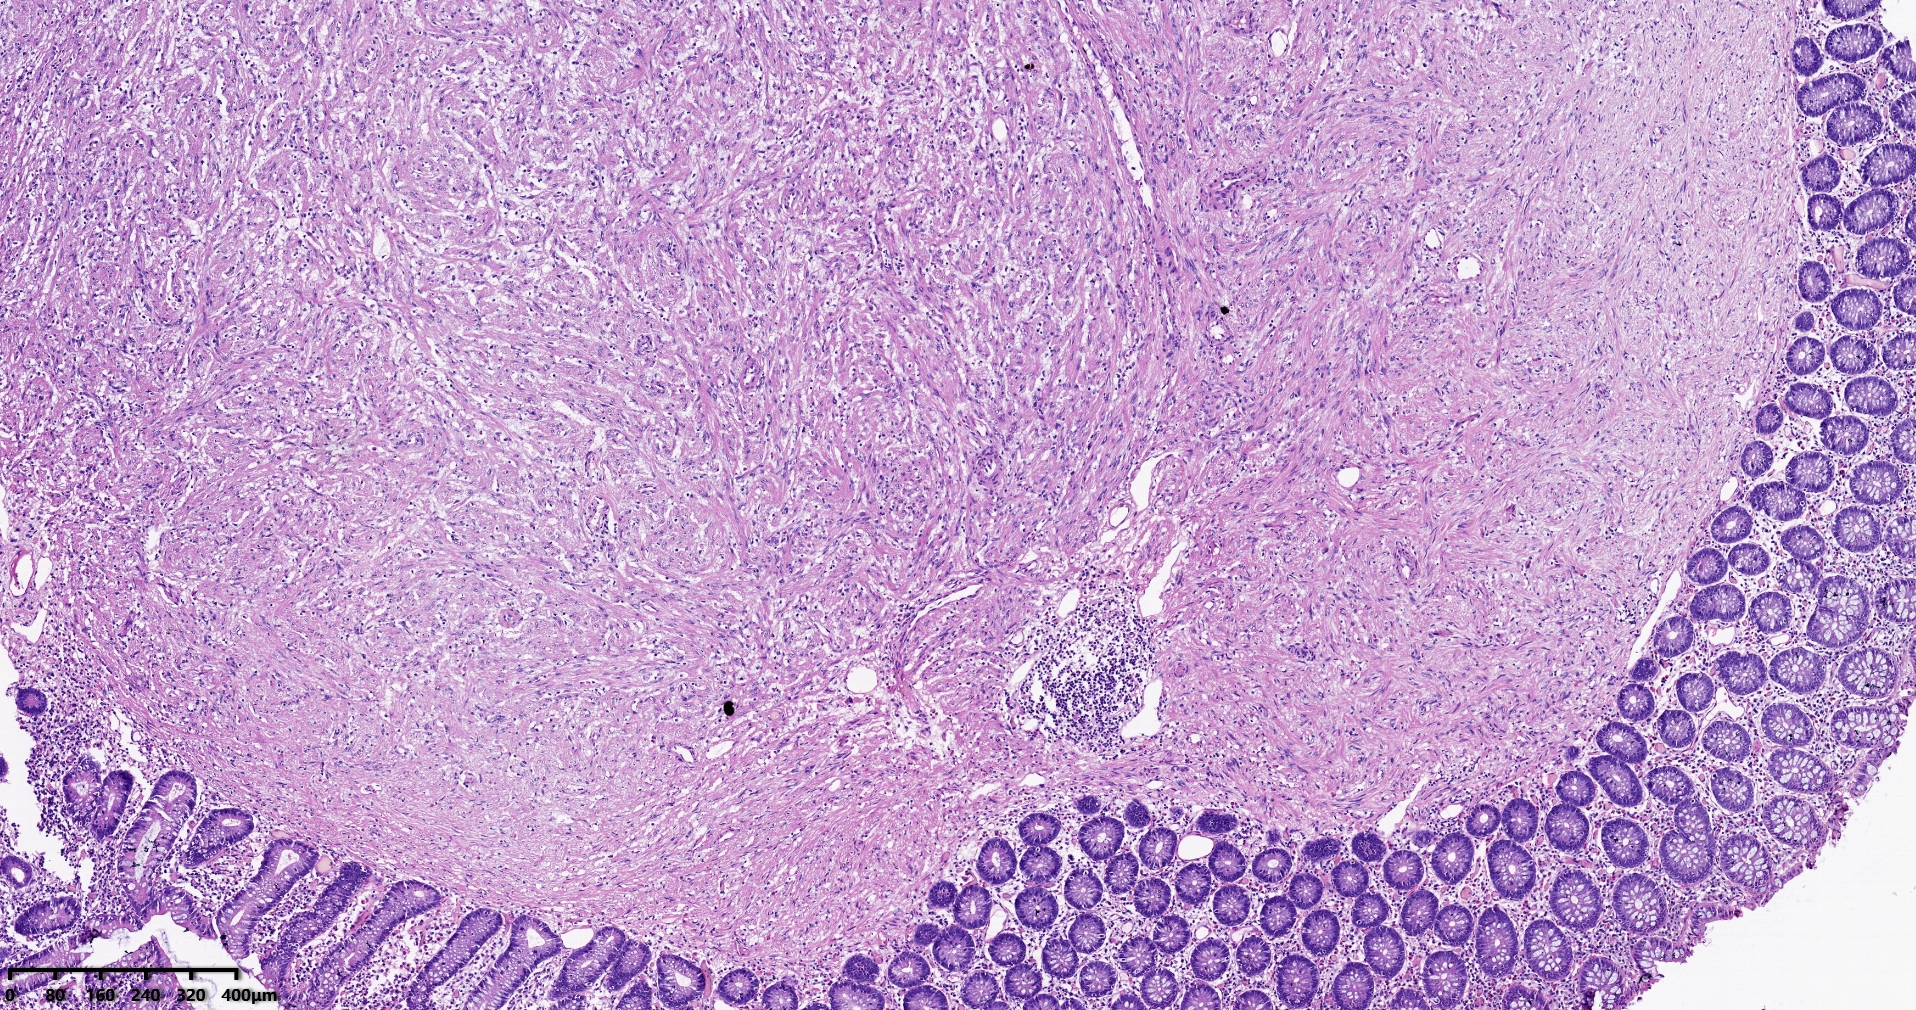

结肠肝曲息肉状肿物,平滑肌瘤?胃肠道间质瘤?炎性纤维性息肉?

性别

男

年龄

56岁

临床诊断

结肠肝曲息肉

一般病史

不详

标本名称

大体所见

灰红色椭圆形息肉一个,直径2.5cm,蒂长0.5cm,切面灰白灰红色,质中。

请路过的老师指教。

考虑间质瘤?

就HE形态而言,间质瘤的可能性要大一些,建议做免疫组化协助鉴别。